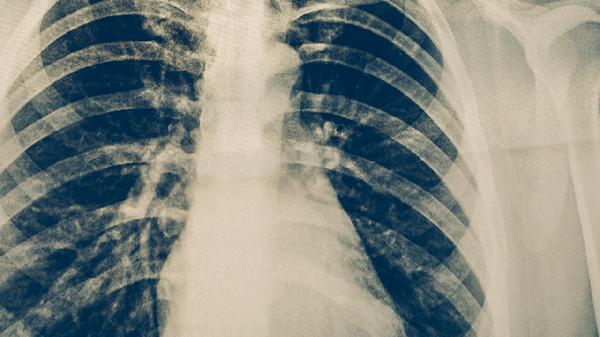

針對(duì)無(wú)法手術(shù)的中央型肺癌或小細(xì)胞肺癌,放射治療可控制局部病灶進(jìn)展。需注意肺結(jié)核活動(dòng)期患者接受放療可能誘發(fā)結(jié)核擴(kuò)散,應(yīng)在放療前至少進(jìn)行2周抗結(jié)核治療。調(diào)強(qiáng)放療技術(shù)可減少對(duì)結(jié)核病灶周圍正常肺組織的照射劑量。

肺癌化療方案需考慮與抗結(jié)核藥物的相互作用,如順鉑注射液可能加重異煙肼的神經(jīng)毒性,培美曲塞二鈉需避免與利福平聯(lián)用。建議兩種治療間隔進(jìn)行,優(yōu)先控制活動(dòng)性結(jié)核后再行化療。化療期間需加強(qiáng)結(jié)核復(fù)發(fā)監(jiān)測(cè)。

對(duì)于驅(qū)動(dòng)基因陽(yáng)性的肺腺癌,表皮生長(zhǎng)因子受體抑制劑如吉非替尼片可顯著延長(zhǎng)生存期。但利福平會(huì)降低多數(shù)靶向藥物血藥濃度,需調(diào)整用藥方案或更換為利福布汀膠囊。治療過(guò)程中需通過(guò)CT評(píng)估結(jié)核病灶與腫瘤的應(yīng)答情況。